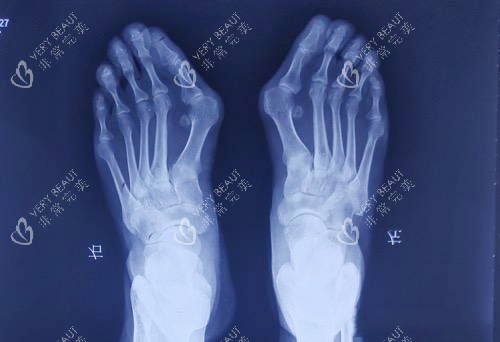

通过朋友推荐,我预约了温建民医师的面诊。温医师是我国中医学学院望京医院骨科管理者,深耕拇外翻治疗近30年,创新的“温氏小切口小创口技术”在业内享有盛誉。面诊当天,温医师仔细检查了我的足部,结合X光片和3D足弓扫描图,给出了特色诊断:“你的拇外翻属于中重度,***跖骨内收角28度,***-2跖骨间夹角15度,伴随轻度足弓塌陷。传统手术需要切开5-8厘米切口,打钢钉固定,术后卧床3周;但用我的小创口技术,1.2厘米切口就能完成截骨,不用钢钉,术后当天可下地。”

大脚骨拍片